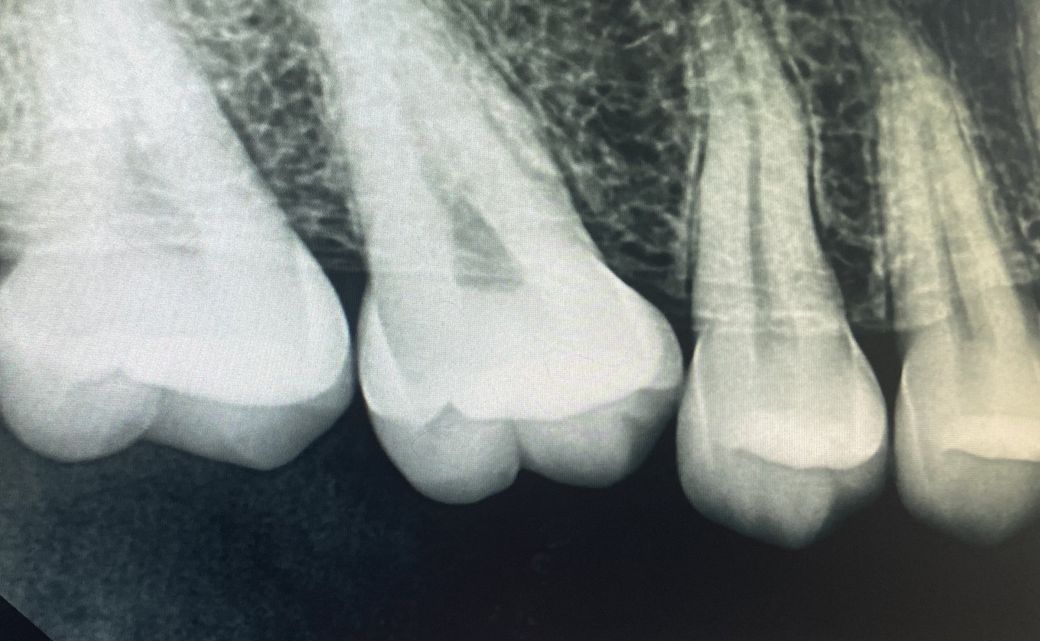

치아가 두동강이 났어요.ㅠㅠ임플란트문의드랴요

작은어금니 두번째깨 위에서 도끼로 내려찍은거마냥 두동강이나서 치료를 해야하는데 임플란트밖에 답이없나요..?ㅠㅠ

• 1번 째 사진

현재 치아가 금이 간 정도에 따라 다를 수 있습니다. 단순히 치아 머리 수준에서 나타난 크랙이라면 간단한 레진 수복에서 신경치료가 가능하나 뿌리까지 크랙이 파급되었다면 발치 밖에 방법이 없습니다. 따라서 전문가와 상의 후 치료하는 것이 필요하고 임신 초기가 아니라면 임플란트 하는데 큰 문제는 없습니다.

치아의 파절이 크게 일어났다면 엄청난 통증이 유발됩니다.

통증이 없는 상태라면 파절선이 크지 않을수 있어요. 파절선이 잇몸뼈 위에 까지만 진행이 되어 있다면 치아를 살려서 사용할수 있습니다.

치아가 두개로 쪼개진경우, 거의 발치를 해야하는경우가 많습니다.